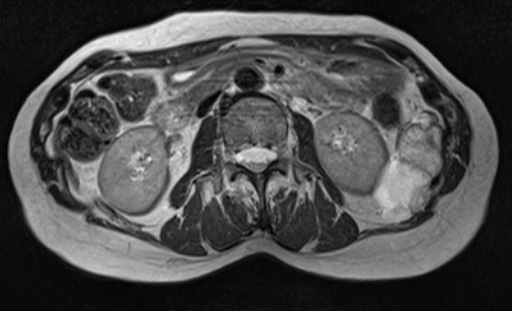

(左腎門部レベル) 図3 左:T1強調横断像

図3 左:T1強調横断像

(in-phase) 図4 T1強調横断像

(out-of-phase) 図5 T2強調横断像

図5 T2強調横断像 図6 拡散強調横断像(b=1000)